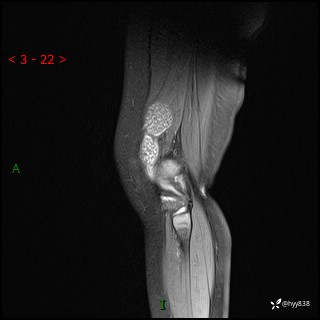

现病史:患儿1月前无明显诱因出现左下肢跛行,伴左膝关节红肿,无发热、咳嗽、恶心、呕吐等症,于当地医院就诊行X线片未提示异常,今至我院门诊就诊,门诊医师拟“跛行待查”收入院。 病后,患儿精神、食欲可,睡眠欠安,大小便通畅,体力体重无明显下降。

左膝MRI平扫